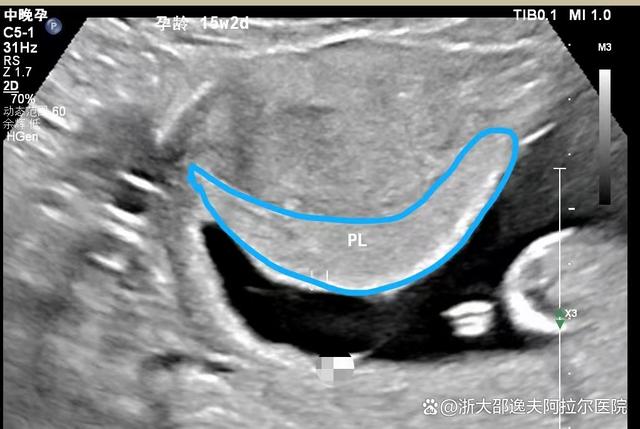

胎盘早熟指的是胎盘在未达到预定期限前过早成熟的现象,这属于一种异常情况胎盘过早成熟会导致血液灌注量减少,从而减少了对胎儿的供氧及营养成分的供应,对胎儿的生长发育造成不利影响具体而言,胎盘早熟可能会引起胎儿宫内窘迫,这表现为胎儿在子宫内出现缺氧状态,严重时可能导致胎儿发育迟缓,甚至危及;胎盘成熟分1,2,3级,23级并不是成熟胎盘,只是说明你的胎盘目前快接近成熟,这也是发育到34周的正常情况,这是正常情况,32周到38周胎儿入骨盆前,这个阶段也正是胎儿转动最明显的时候,发育最快的时候,只要你不感觉有规则的宫缩和胸闷就没问题,如果羊水正常也没必要吸氧,胎盘3级只要没有钙化就;胎盘早熟的原因多种多样其中,高血压是首要因素,包括妊娠高血压综合征特别是重度妊高征原发性高血压以及慢性肾炎合并高血压等此外,机械性因素也不可忽视,如腹部直接受到撞击如汽车撞击公交车急刹车碰撞跌倒时腹壁先着地等以及外力的过度作用如殴打外倒转纠正胎位受阻而用力过大;因缺氧窒息而死亡胎盘是胎儿的“营养库”,母体通过胎盘为胎儿提供营养和氧气,胎盘成熟度一般分为三级,越高就表示越成熟正常情况下胎儿的生长速度与胎盘的成熟度应该是同步增长的,因此,胎盘早熟属于异常情况专家提示首先做一个详细的孕期检查,以确定胎盘早熟的原因,以便对症治疗;正常情况下胎儿足月以后胎盘成熟度才会达到23度,胎儿的生长速度与胎盘的成熟度应该是同步增长的胎盘过早成熟属于异常情况,过早成熟的胎盘会减少血液的灌注量,从而减少对胎儿的供氧及营养成分,影响胎儿的生长发育,可以出现胎儿宫内窘迫,发育迟缓,甚至死亡胎盘早熟的原因有多种,有了胎盘早熟的现象;胎盘早熟的原因主要有以下几点孕期营养状况不佳营养摄入严重不足孕妇在整个孕期持续呕吐,无法正常进食,导致营养摄入不足,直接影响胎盘发育,促使胎盘过早成熟营养物质转化问题母亲摄入的营养物质大量转化为自身生理活动所需的能量和物质,胎儿能够吸收的营养相对较少,也可能导致胎盘早熟营养素缺乏特别是蛋白质维生素和矿物质等关键。